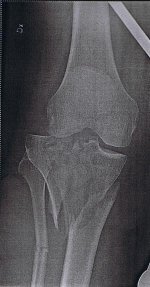

Vecka 44 kommer jag bli inlagd på sjukhuset igen. Kan fortfarande inte böja knät mer än ca 60 grader, så under narkos kommer doktorn bryta upp ärrvävnaden som bildats i knät genom att knäcka upp det. Dvs han böjer knät när jag sover så långt det går![]()